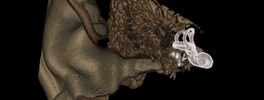

CT Scan Internal Ear